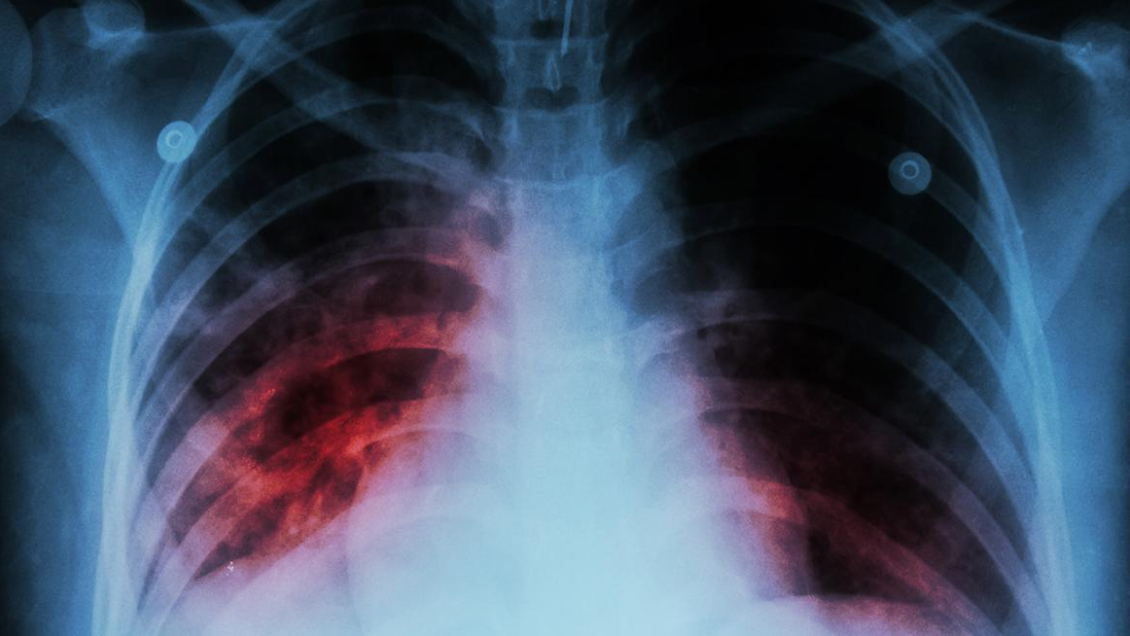

Casi 50 trabajadores de la salud se infectaron de tuberculosis en Venezuela

Referencial

Al menos 46 trabajadores sanitarios del sector público de Venezuela se infectaron de tuberculosis entre enero y junio de este año, según un reporte de la Encuesta Nacional de Hospitales (ENH) publicado este jueves y elaborado por la ONG Médicos por la Salud.